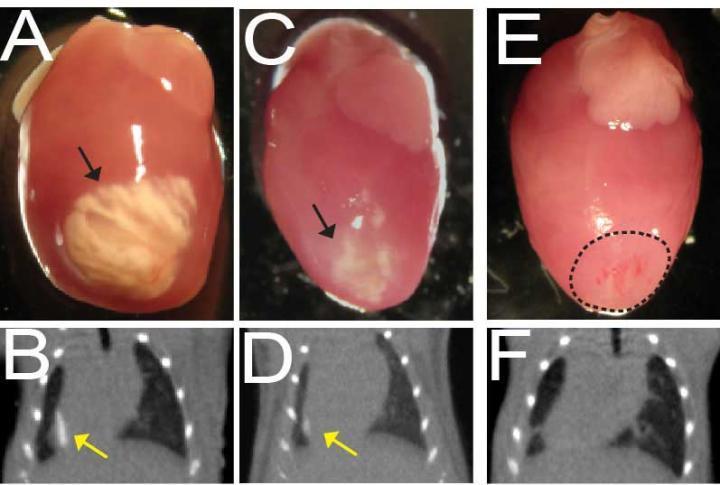

Отложение солей кальция в сердце чаще всего развивается после инфаркта или воспаления миокарда . К факторам, которые способствуют переходу этого макроэлемента из крови в ткани, относятся:

Накопление углекислоты в таких тканях сопровождается образованием углекислого кальция . Дистрофическое обызвествление встречается в гиализированной соединительной ткани, особенно во вновь образованной при . . .

Соли кальция в сердце плода Автор: admin 13 .05 .2019 13 .05 .2019 Препараты для молодости Гиперэхогенный фокус - это термин, говорящий о повышенной эхогенности (яркости) небольшого участка сердечной мышцы на ультразвуковом . . .